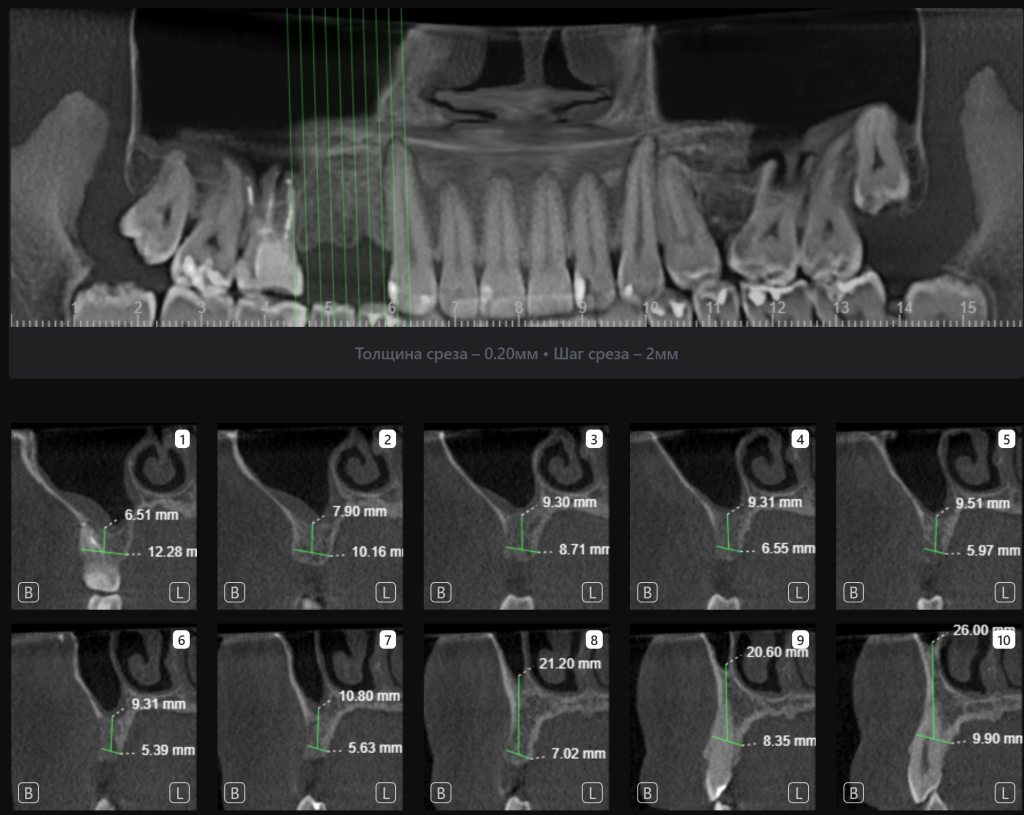

«Имплантологический отчет», созданный искусственным интеллектом Diagnocat, помогает определить оптимальные размер и расположение имплантата в соответствии с индивидуальными особенностями анатомии